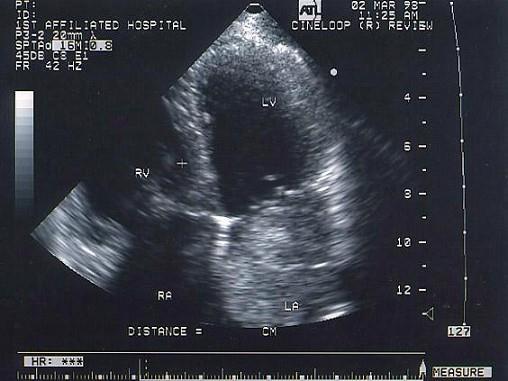

该病例最可能的诊断?(?)A.血栓B.房间隔膨胀瘤C.黏液瘤D.赘生物E.以上都不是

问题 该病例最可能的诊断?(?)

选项 A.血栓 B.房间隔膨胀瘤 C.黏液瘤 D.赘生物 E.以上都不是

答案 C